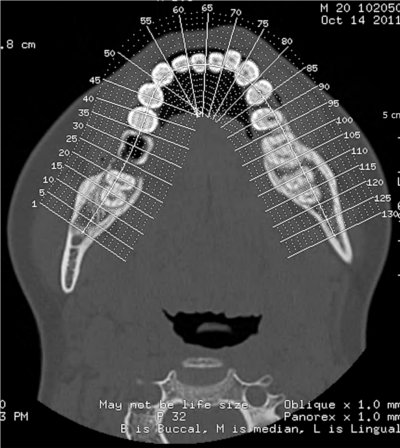

SCANNER DENTAIRE (DENTALSCANNER)

Les nouvelles générations de scanner permettent de faire une acquisition d’un volume global d’une partie du corps et de travailler à l’intérieur de ce volume en isolant une structure anatomique donnée et de l’explorer dans tous les plans de l’espace.

Grace à la technique de seuillage il est possible de dissocier progressivement les dents des structures osseuses environnantes dans le volume donné.